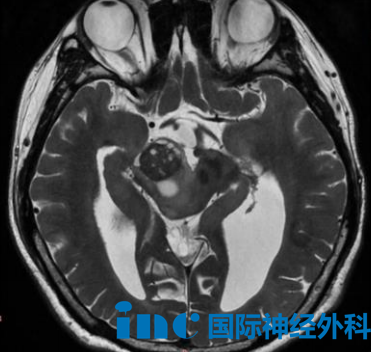

巴特朗菲教授抵达苏州后,立即在苏州大学附属儿童医院和苏州大学附属第四医院开展密集的医疗活动。在紧凑的行程中,他先后为7位疑难脑肿瘤患者完成深入的面诊或远程视频会诊,并为次日即将接受示范手术的患者进行术前评估。会诊病例涵盖脑干、小脑、桥前池、脑室内、桥小脑角区等多个复杂部位的神经系统疾病。

巴特朗菲教授仔细分析每位患者的影像学资料,结合具体临床表现和功能状态,以数据化、个体化的方式评估每例手术的可行性、风险程度和预期效果,为患者提供明确的治疗方向。